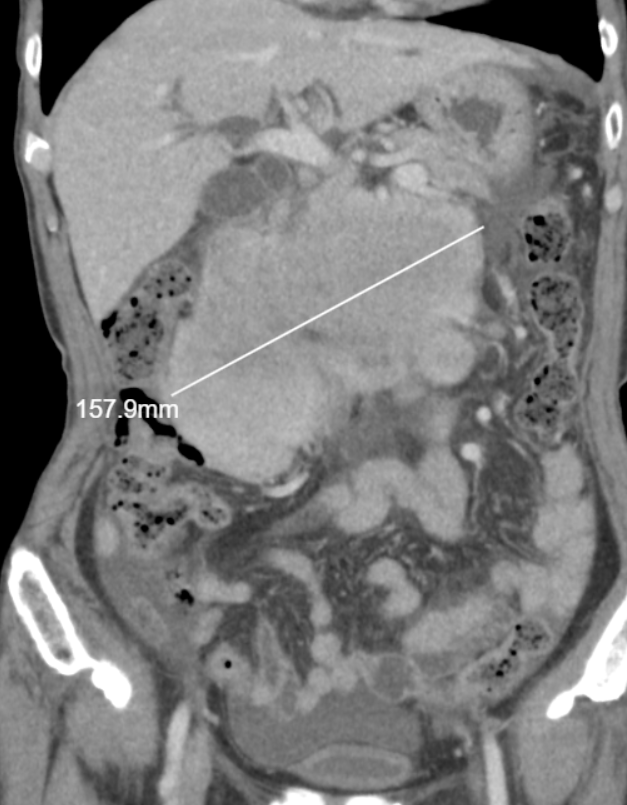

혈액검사에서 큰 이상소견 보이지 않아, 추가로 CT 당일 시행하였습니다. 시행한 복부 CT상에서 불편감을 호소하시는 부위에 약 16cm 크기의 큰 종양이 확인되었으며, 주변 임파선 크기 증가 및 복수가 확인되어, 림프증식성 질환이나 육종등의 종양이 주변 임파선 및 복막으로 전이되었을 가능성이 확인되었습니다.

• 복부CT 관상면: 종양 크기 157.9mm 측정 복부CT 관상면: 종양 크기 157.9mm 측정